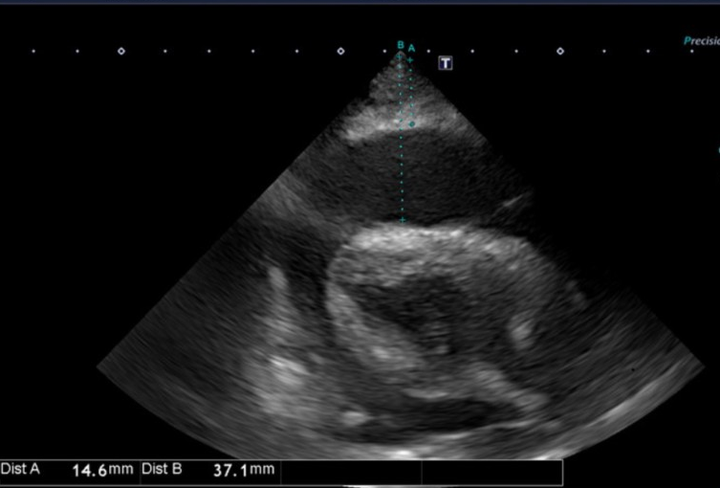

上の画像は犬の心臓をエコー検査で撮影したものです。

心臓の周囲(心嚢腔)に液体がたまり、心臓が押しつぶされるように圧迫されています。

これが 心タンポナーデ と呼ばれる状態で、命に関わる危険な病態です⚠️

• 心エコー検査で心嚢内に液体が貯留しているのを確認(今回の画像のように黒く抜けて見える部分が液体)